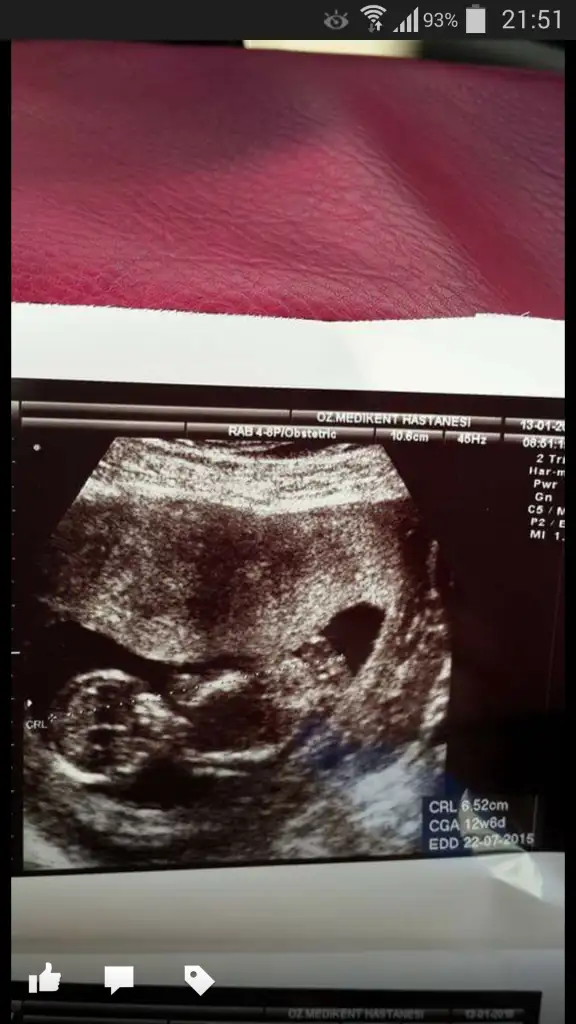

Kızlar sizce cinsiyeti ne bilenler söyleyebilir mi

BENCE ERKEK :)Kızlar sizce cinsiyeti ne bilenler söyleyebilir mi

yorum yapan arkadaşlara tşk ederim :)%90 erkek dedi dr :)[/QUO